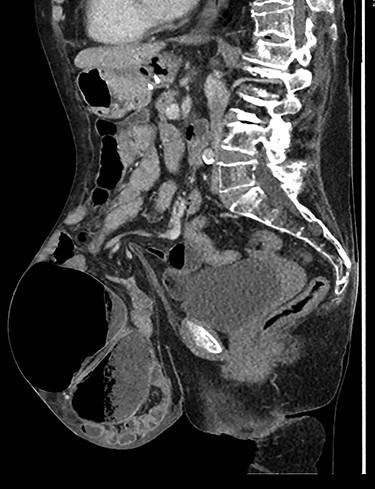

Caecal volvulus through wide-necked abdominal wall defect with small amount of free fluid in pelvis (sagittal).

A clinical diagnosis of bowel obstruction was made; she underwent a CT abdomen/pelvis with contrast, which demonstrated a large bowel obstruction within the hernia not caused by the hernial defect but thought likely due to volvulus of the caecum (Figs. 1 and 2).